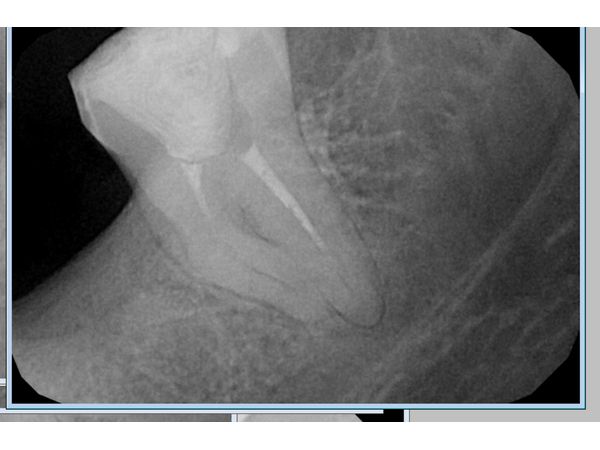

По результатам рентгена, у женщины обнаружили сложную анатомию каналов, при которой качественно вылечить зуб в условиях районной поликлиники невозможно. Чтобы пациентка смогла его сохранить и в дальнейшем поставить протез, ей предложили обратиться в другую клинику.

Исследование показало следы пломбировочного материала в медиальном (щёчном) корне зуба и запломбированный на две трети дистальный канал.

По данным снимка, оснований для отказа от повторного лечения не было, несмотря на аномальный изгиб медиального корня.